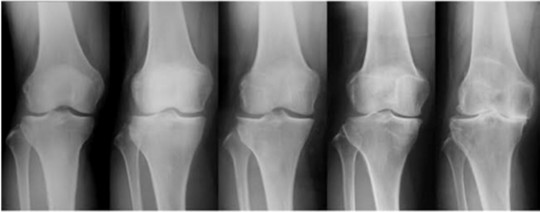

40代の膝痛は変形性膝関節症の初期です

膝が痛い方の多くは階段を降りているときに、膝が内側に入ることが多くみられます。

この膝が内側に入ることが膝の関節の中で剪断力が生まれキズをつけてしまう事がある事は有名な話になります。

これは階段の上り下りだけでなく、歩くという動作でも膝は内側に入ります。

だから、膝が内側にはいるという事は、一歩歩けば膝にかかるストレスが通常より高くなる。

この膝が内側に入ることを繰り返す事が膝を痛める原因の1つになると言われています。

膝関節痛は膝だけの問題ではなく、膝がどう動きているのか?

「変形しているから仕方ない!」ではなく、動作が変われば必ず膝の状態は変わります。

まだ40~50代の初期の変形性関節症なら、まだ全然間に合います。